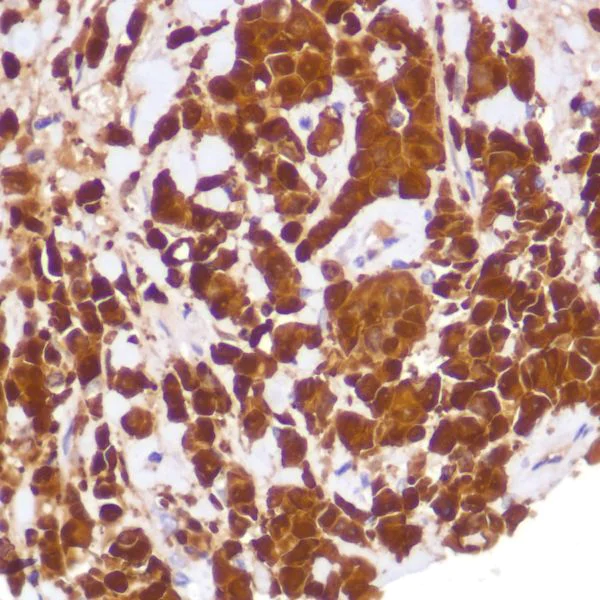

Immunohistochemistry (Formalin/PFA-fixed paraffin-embedded sections) - Anti-Indoleamine 2, 3-dioxygenase antibody [SP260] - C-terminal (AB228468)

Formalin-fixed paraffin-embedded human tonsil tissue stained for Indoleamine 2 3-dioxygenase with ab228468 at 1/100 dilution in immunohistochemical analysis.